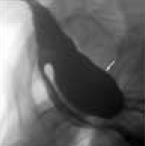

Zenker Diverticulum

<div id="article-content-body"><p><a href="http://imaging.cmpmedica.com/consultantlive/images/articles/2006/12012006/0612ConPCZenker.jpg"><img...